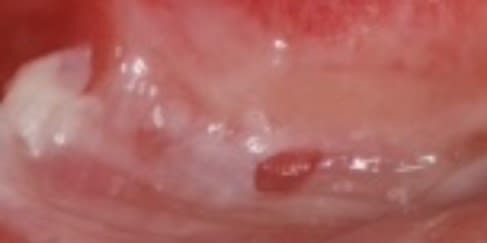

1/ l aspect que ça a

je pense à une brulure au paroex pour l aspect blanc filandreux , et probablement à un double canal resté vivant pour ce qui est de la douleur au froid .

Parfois chez un patient qui si prête tu peux éplucher l'épithélium, il faut muqueuse sèche, ta compresse ou ton coton va "coller" et enlever la couche superficielle, après sa ressemble à ton truc sur la zone "décollée", c'est douloureux et guérit lentement mais surement.

Quand tu enlèves la compresse tu sens que ça colle.

Ça fait plus penser à une brûlure ou une réaction à un produit irritant ou à un peeling comme décrit par vulpi... Ou les trois...